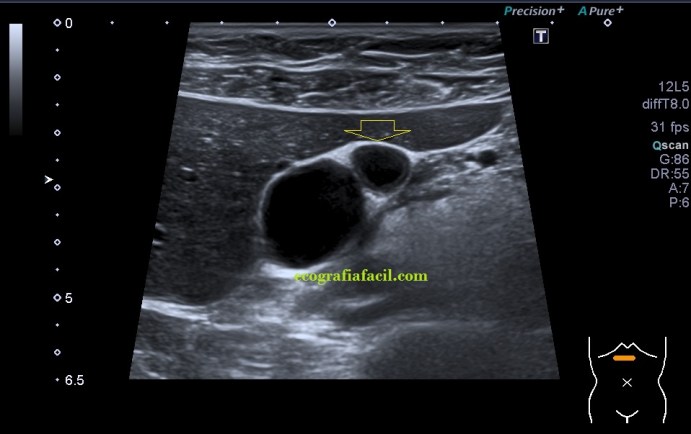

Sumado a esta peculiar presentación encontramos que en la curvatura sacular, en el fundus de la vesícula, «en la punta» que se objetiva en la imagen 2, percibí como si la pared en ese punto estuviera ligeramente engrosada, pero no terminaba de verlo como yo quería así que cambié la sonda, de cónvex a lineal, adapté los parámetros o ajustes ecográficos y la imagen de la pantalla era preciosa, se veía la imagen sacular, muy definida, gracias a la alta frecuencia de la sonda lineal, con una definición muy importante que me permitió documentar como en la pared de la vesícula, imagen 4, existía engrosamiento mural. Se usa el cónvex virtual o trapezoidal, como ajuste que permite ampliar el scan range de la pantalla con el uso de la sonda lineal.

Dicho engrosamiento, una vez revisada la historia clínica estaba descrito como adenomiomatosis, y ecográficamente era un engrosamiento mural, parcial (solo era en una porción de la vesícula), hiperecogénico y homogéneo, perfectamente visible en la imagen 4, señalada con una flecha amarilla fina.

En el doppler (imagen 5) no había actividad, pero esto hay que comprobarlo siempre ya que en ocasiones, la literatura habla de actividad vascular del engrosamiento mural. Además podemos encontrar sendos artefactos ecográficos, como el aliasing y la cola de cometa, provocados por estos focos adenomiomatosos, que en este caso específico, no se objetivaron, una pena…la verdad.

Si la paciente no hubiera estado diagnosticada, el hallazgo es compatible con otra patologías como puede ser el barro biliar, algún tipo de neoplasia vesicular o la colecistitis, por eso ante este tipo de semiologías no compatibles con la normalidad, siempre consultamos con la radióloga para que decida sobre ampliaciones de estudio con posibles alternativas de estudios de imagen, como puede ser la Colangio RM. Esta patología puede ser asintomática. También puede presentarse con otras figuras patológicas como las colelitiasis.